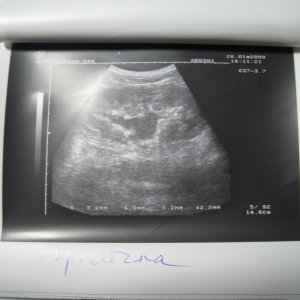

Доктор здраствуйте! мне 23 годаОколо полугода назад лежал на обследовнии в нефрологии,где был посиавлен диагноз:хр,пиелонефрит обеих почек,МКБ,микролиты обеих почек 2-4мм,наиболее крупный справа 4 мм!Было рекомендовано:курсам пить пролит,цистон,урологические сборы и тд!Все ето я принимал,почки особо не беспокоили если тока изредка небольши тупые боли в пояснице по утрам и все!Вчера решил сделать узи почек:диагноз был поставлен следующий:гидронефроз правой почки 1 степени,(врач сказал что лоханка в правой почке увеличена до 40 мм из за МКБ,лоханка левой почки 18 мм,остальные параметры в норме)микролиты обеих почек 2-4 мм,хр,пиелонефрит обеих почек!!количество мочи в течении дня нормальное,удалось сдать анализы мочи(общий и по Нечипаренко!Общий:

Чувствую себя нормально,небольшая слабость,утомляемость а так более менее!посоветуйте что нужно и можно делать в моей ситуации!какие препараты следует пропить и тд!урологов в городе нет,буду ждать ваших рекомендаций!файл с узи приложил